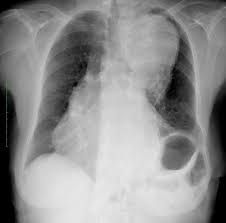

Ortner’s syndrome is also known as cardiovocal syndrome. It refers to the hoarseness of sound as a consequence of cardiovascular disorder. The enlarged cardiac structure, most commonly left atrial hypertrophy, induces mechanical compression of left recurrent laryngeal nerve, thereby causing hoarseness of sound. Reference: https://en.wikipedia.org/wiki/Ortner%27s_syndrome Image via: https://radiopaedia.org/articles/ortner-syndrome